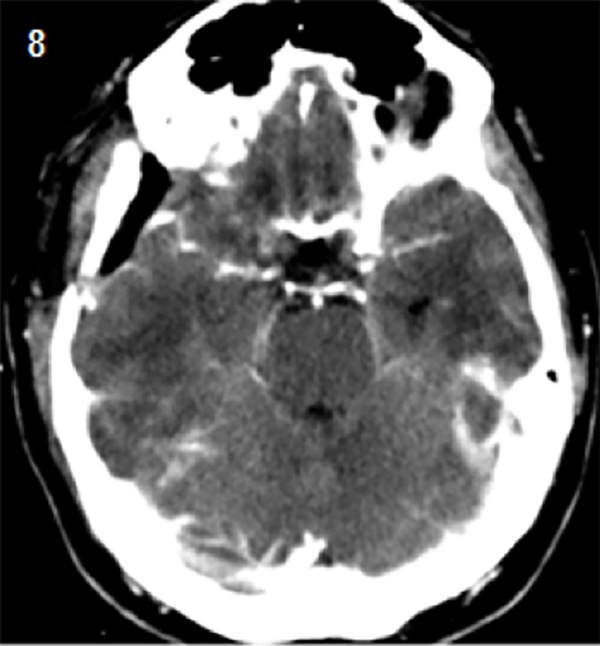

Tomografía computada de encéfalo con contraste, realizada 24 horas después del procedimiento quirúrgico (Figura 8).

Figura 8. Tomografía 24 hs.